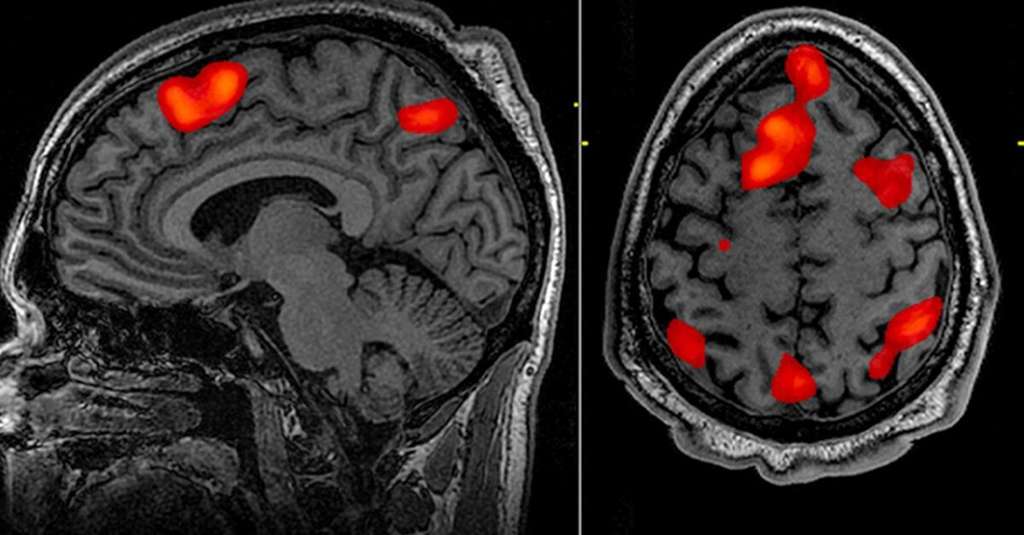

由fMRI扫描生成的大脑活动图,红色区域表示统计上显著的激活。SPM为此类数据的分析提供了标准化框架

SPM是什么?

SPM指的是一个概念框架和一套据此开发的开源软件包,用于对功能性脑成像数据序列(如fMRI, PET, MEG/EEG)进行统计分析。其核心思想是在大脑的每一个体素(voxel,即三维像素)上进行统计检验,从而生成一个显示统计显著性区域的“参数图”。这个软件包由中心的核心人物Karl Friston 在中心成立早期于Hammersmith医院时期便开始编写,并随着中心的发展不断完善。